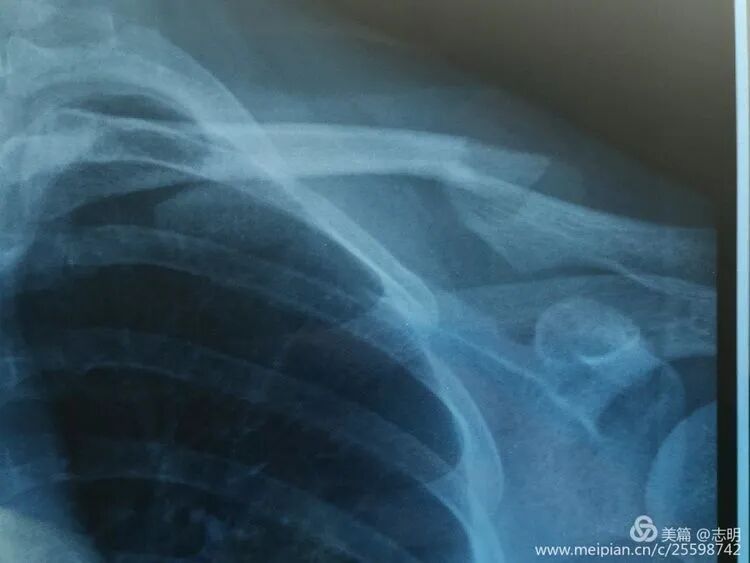

(X-ray showing pre-reduction fracture).

(Initial fluoroscopic view of the fracture).(Another pre-reduction X-ray).

(Post-fixation X-ray).(Healed fracture X-ray).(Another post-fixation X-ray).

(Post-fixation X-ray showing the plate and screws in place).(Another post-fixation X-ray).